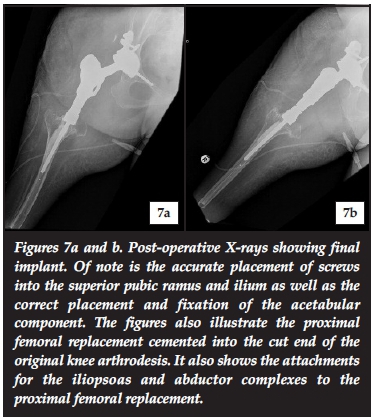

The surgery was performed with the patient bolstered in the lateral position and a lateral approach was used to gain access to the hip joint. After removal of existing hardware and the proximal femur, the novel acetabulum was created using the premade reaming jigs. The acetabular component was fitted into this structure using screws accurately placed by the customised drill guide (Figures 7a and b, and Figure 8). An Avantage dual-mobility cup was cemented into the acetabular component and a proximal femur replacement (LRS Implants, Cape Town) was performed with repair of the soft tissues.7